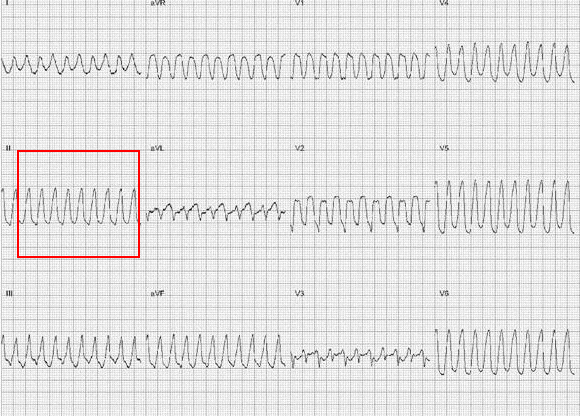

10. 室速诊断诀窍:抓II导联

什么是同步心电图心电图学不会、记不住?这个合集very good!_https://www.jmylbn.com_新闻资讯_第26张什么是同步心电图心电图学不会、记不住?这个合集very good!_https://www.jmylbn.com_新闻资讯_第27张